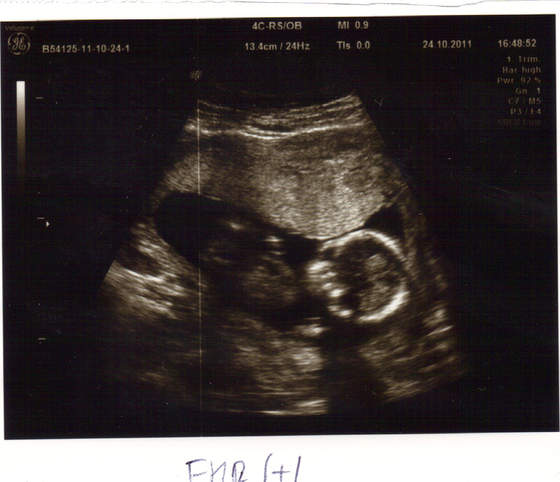

No to my już po wizycie, dzięki za kciuki Dziewczyny! Dzidziołek ma prawie 10cm (94mm) i wierci się niesamowicie!:-)Natomiast mamusia dostała Isoptin żeby obniżyć zbyt wysokie tętno-gin powiedział, że na maleństwo nie ma on wpływu, a jeszcze do tego zapobiega skurczom macicy, więc powinno być już ok. Załączam zdjęcie maleństwa, którego o mały włos znowu bym nie dostała, bo gin kupił nowy aparat do usg i nie wszystko jeszcze opanował;-):

dzidziołek.jpg